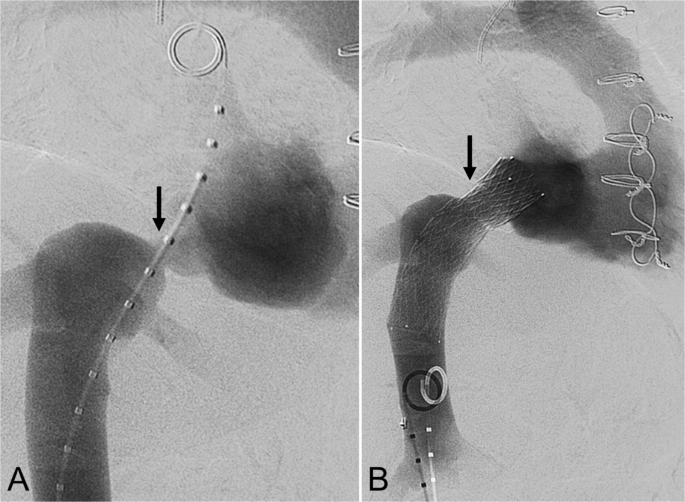

一名68岁的女性,在因扩张型缺血性心肌病(ICM)接受OHT手术后27天,出现顽固性双下肢水肿。经胸超声心动图显示腔静脉-心房吻合口狭窄程度超过85%,下腔静脉(IVC)造影证实狭窄程度超过75%(图1A)。在狭窄部位放置了一枚20毫米×80毫米的Venovo支架(BD Bard;新泽西州Franklin Lakes),并使用16毫米球囊进行扩张。术后造影显示IVC-右心房(RA)血流顺畅(图1B)。血管内超声(IVUS)确认支架扩张效果良好。水肿在9天内消退。140天时的计算机断层扫描(CTV)显示支架通畅。

一名68岁的女性,在因扩张型缺血性心肌病接受OHT手术后27天,出现药物难以控制的双下肢水肿。A 下腔静脉造影显示吻合口狭窄程度超过75%(黑色箭头)。B 重建后的造影显示20毫米×80毫米的Venovo支架(黑色箭头)已放置到位,狭窄得到缓解